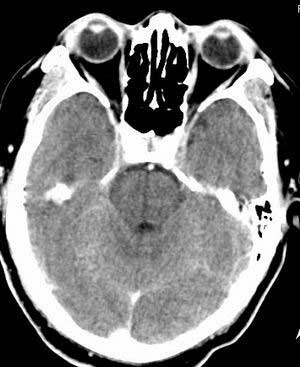

双侧乳突蜂房密度呈气体样,慢性乳突炎可能性不大,

双侧颞叶脑实质密度均匀未见异常密度灶,

考虑颅内未见异常。

条状高密度为小脑幕吧

条状高密度为小脑幕

横窦乙状窦。

增强的横窦乙状窦。